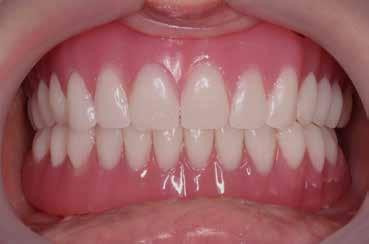

1. ábra: Műtét előtti fogászati panorámafelvétel, amelyen a hiányzó felső állcsont jobb első premolárisát és a szabad véggel rendelkező hidat láthatjuk. — 2. ábra: Az implantátum méreteinek megtervezése CBCT-vel. 3. ábra: Bukkális lágyrészdefektus. — 4. ábra: A biológiai szélesség értékelése a vertikális lágyszövetvastagság alapján. 5. ábra: Palatinális „tekercslebeny” – Palatal roll flap. — 6. ábra: Bredent medical copaSKY 4x10 implantátumbeültetés. 7. ábra: Szubkresztális implantátumbeültetés a várható biológiai szélességnek megfelelően.

8. ábra: Egyéni ínyformázó titánbázison, tulipán alakú emergenciaprofillal. — 9. a. ábra: A sebzárás okkluzális nézete.

bukkális nézete.

(2. ábra). A lágyszövetek értékelése Seibert szerinti I. osztályú csontdefektust állapított meg (3. ábra), ezért a beavatkozáskor palatinális „tekercslebenyt” preparáltunk (palatal roll flap), és implantációt végeztünk, hogy kompenzálni tudjuk a bukkális lágyszövet-behúzódást. Megmértük a vertikális lágyszövetvastagságot, és úgy terveztük, hogy a szubkresztális implantátum beültetése összhangban legyen a biológiai szélesség kialakulásával a transzgingivális gyógyulási periódus alatt (4. ábra)

uni.fit titánalapra (bredent medical). Az implantátum körül a bukkális lágyszövet megfelelő vastagságot és kedvező ínykontúrt mutatott (12. a–b. ábra). Az egyedi ínyformázó eltávolítása után egészséges implantátum körüli lágyrészgallér

volt megfigyelhető (13–14. ábra), ezen kívül közvetlenül a műtét előtt intraorális vizsgálatot végeztünk a lágyszöveti profil megállapítása érdekében. Ezt követte a scanbody behelyezése, így digitális lenyomat készült az implantátum pozíciójáról (15. ábra). Ugyanezzel a technikával rögzítettük az antagonista fogívet és a harapást is. Az így kapott STL-fájlokat digitálisan továbbítottuk a fogtechnikai laboratóriumba. A titánalapra PMMA ideiglenes koronát készítettünk a proximális és marginális illeszkedés ellenőrzése érdekében, valamint a megfelelő harapás elérése céljából (16–17. ábra) Miután az összes igazítás elkészült, ismételt vizsgálatot végeztünk. A végleges hibrid csavarrögzítésű, teljes kontúrú cirkóniumkoronát titánalapon erősen polírozott szubgingivális résszel készítettük el, és 25 Ncm nyomatékra húztuk (18. ábra). Kiváló árnyalategyezést és klinikai eredményt